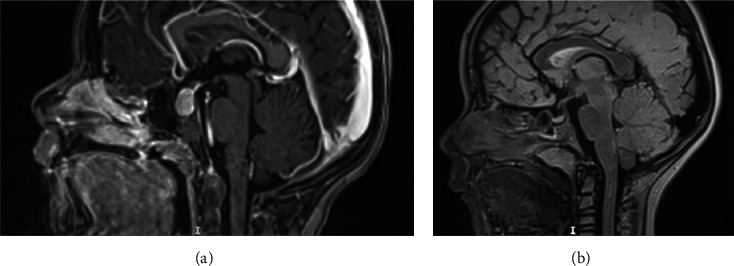

儿童慢性甲状腺功能减退症的主要表现包括生长停滞、骨骼成熟延迟和青春期延迟。1960年,Van Wyk和Grumbach报道了三名患有甲状腺功能减退症的女孩,她们同时患有不完全异性性早熟(乳房发育早、月经初潮、无阴毛)、半乳糖性闭经、骨龄延迟和垂体增大。在接受适当的甲状腺激素替代治疗后,所有异常情况都得到了缓解。多年来,越来越多的病例报道让人们对范-维克-格伦巴赫综合征(VWGS)的临床、生化和放射学表型有了更准确的认识。这些不同的临床表现被认为是独特的病理生理过程所致,而促甲状腺激素(TSH)是其中的关键因素。我们描述了两名患有严重自身免疫性甲状腺炎和 VWGS 的患者(一男一女)的病例。这两名患者的临床、生化和放射影像学特征相似,包括生长发育障碍、无临床甲状腺肿、促甲状腺激素(TSH)浓度明显升高(>100 mIU/L)、检测不到游离甲状腺素水平、甲状腺球蛋白水平 "正常"、促卵泡激素(FSH)和催乳素水平高、青春期前黄体生成素(LH)水平高、骨龄延迟和垂体增生。两名患者表现出差异,尤其是女性患者没有临床青春期发育、中度贫血、肾功能异常以及通过超声波检查发现的中度甲状腺肿。甲状腺素替代疗法逆转了 VWGS 表型和甲状腺功能减退症,患者的生长速度令人满意,甲状腺功能严格正常,6 个月随访时通过磁共振成像检测到垂体大小正常。

The primary manifestations of chronic hypothyroidism in children include growth arrest, delayed skeletal maturity, and delayed puberty. In 1960, Van Wyk and Grumbach reported three girls with hypothyroidism and a combination of incomplete isosexual precocious puberty (early breast development, menstruation, and absence of pubic hair), galactorrhea, delayed bone age, and pituitary enlargement. All abnormalities regressed after appropriate thyroid hormone replacement therapy. Over the years, an increasing number of reported cases has allowed for a more precise understanding of the clinical, biochemical, and radiological phenotypes of the Van Wyk-Grumbach syndrome (VWGS). These varying clinical manifestations are thought to result from a unique pathophysiological process where the thyroid-stimulating hormone (TSH) is a key element. We describe the cases of two patients (a boy and a girl) with severe autoimmune thyroiditis and VWGS. The clinical, biochemical, and radiological imaging characteristics were similar in both patients and included growth failure, absence of clinical goiter, markedly elevated TSH concentrations >100 mIU/L, undetectable free thyroxine levels, "normal" thyroglobulin levels, high follicle-stimulating hormone (FSH) and prolactin levels, prepubertal levels of luteinizing hormone (LH), delayed bone age, and hyperplasia of the pituitary gland. The two patients displayed differences, especially in the absence of clinical pubertal development, moderate anemia, abnormal renal function, and moderate goiter detected via ultrasonography (in the female patient). Thyroxine replacement therapy reversed the VWGS phenotype and hypothyroidism, with satisfactory growth velocity, strictly normal thyroid function, and normal pituitary size detected via magnetic resonance imaging at the 6-month follow-up visit.